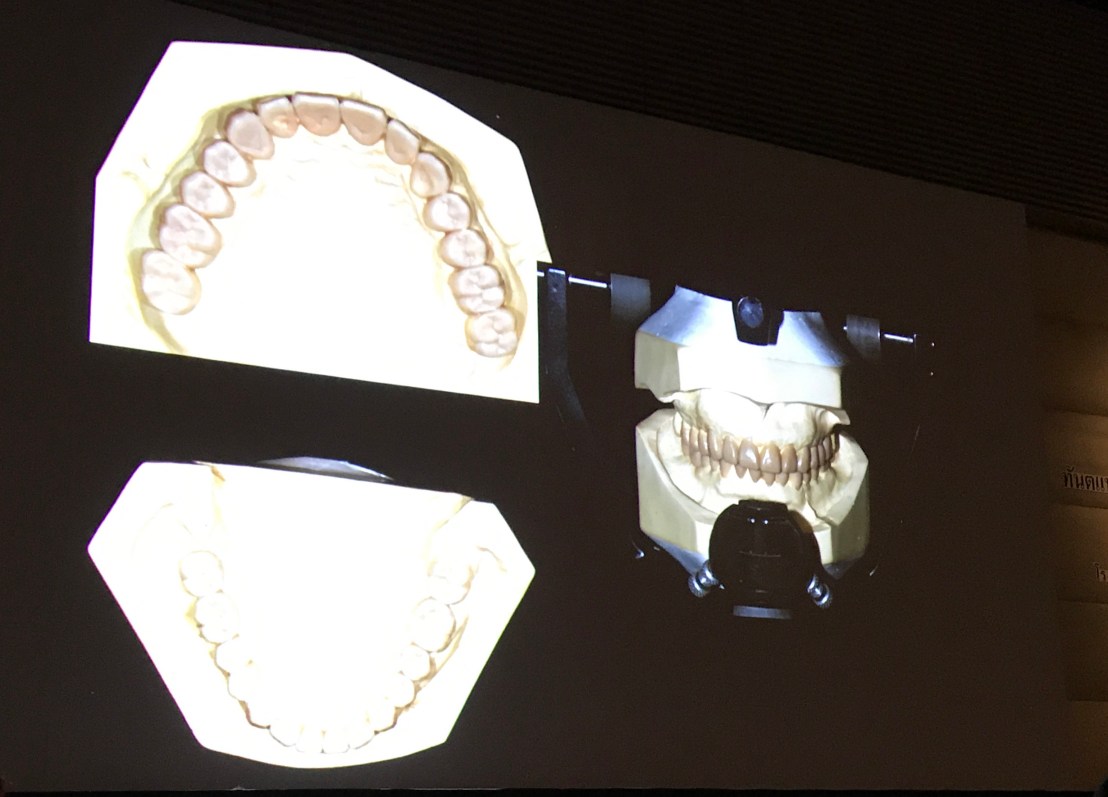

Transfer Facebow เข้า Articulator

เป็นการบอกทางอ้อมว่า ถ้าจะทำ case FMR ต้องมีเครื่องมือเหล่านี้ในคลินิก

โดยสรุปตรงนี้คือ Digital จะเข้ามาทำงานตั้งแต่การออกแบบ/ Wax up/ Mounting เข้า Articulator/กลึงชิ้นงานเลยครับ

ใช้ครับ ท่านฟังไม่ผิด คือ ใช้ Software Wax up กันเลย โดยไม่ต้องทำบน cast ปูน

ใช่ครับ ท่านฟังไม่ผิด ที่เห็นนี่คือ ใช้ Software เข้า Virtual Articulator ครับ

ปรับมุม Incisal table และมุม Condylar inclination ได้เหมือน Articulator ปกติ และพิเศษไปกว่านั้น คือ มัน movement ได้โดยการเคลื่อน lower arm ได้เหมือน mandible จริงครับ (Articulator ที่พวกเราใช้กัน ไม่ว่าจะเป็น arcon หรือ non-arcon type ต้องเคลื่อน cast บนที่ติดกับ upper arm เท่านั้น ไม่สามารถขยับ lower arm ให้เหมือนคนจริงๆ ได้)